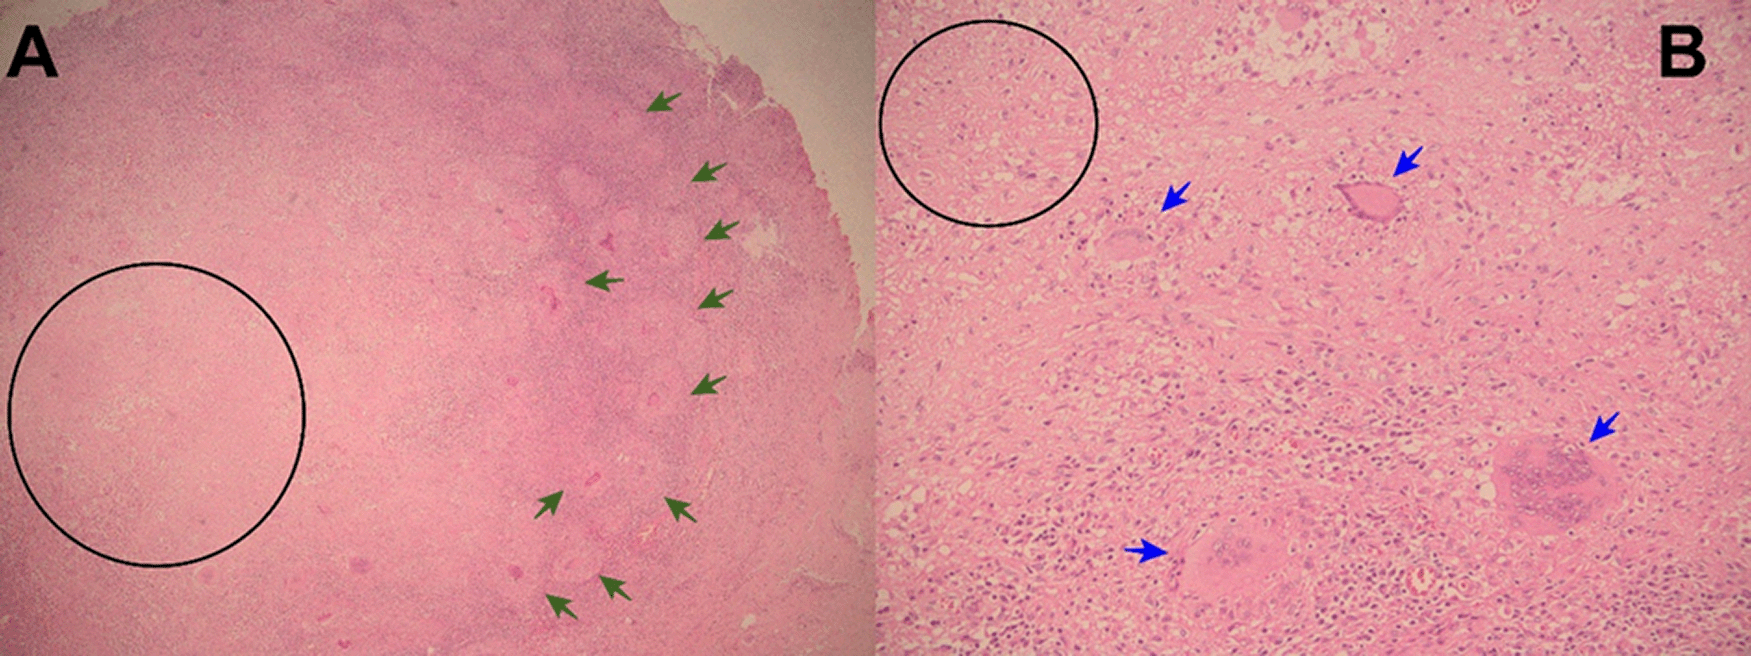

Evolution. One hour after surgery, because of clinical signs of hemodynamic shock, the patient was transferred to the intensive care unit (ICU). At ICU admission the patient was febrile (38.5°C), with hypotension (arterial blood pressure 70/30 mmHg), tachycardia (116 beats per minute), tachypnea (26 breathes per minute) without hypoxia (peripheric saturation 96% in ambient-air), severe dehydration with cold and mottled skin with prolonged capillary refill time, with sleepiness but respondent to verbal stimulus; the abdomen was distended and painful, with reduced intestinal peristalsis, and the wound (8 cm in length) of the recent surgery was macroscopically in order and percutaneous drainages in both iliac fossa were in place showing serohematic secretion. A broad-spectrum antibiotic therapy (meropenem and metronidazole) was started, together with supportive treatment including vasopressors (noradrenaline) and fluid replacement. After a week of the above-mentioned treatment, the clinical condition of the patient was improved and at the seventh day after the surgery, the patient was transferred from the ICU to another hospital division. Then, the result of the histopathological exams of samples collected during surgery showed: “chronic granulomatous inflammation, granulomas, extensive caseous necrosis and Langhans giant multinucleated cells; Ziehl-Neelsen (ZN) stain for Acid Fast Bacilli (AFB) negative”, and a diagnosis of abdominal TB was performed (Figures 1-3). Based on this result quadruple anti-tuberculous treatment (isoniazid 5 mg/kg, rifampicin 10 mg/kg, ethambutol 20 mg/kg, pyrazinamide 25 mg/kg) was initiated in concordance with Peruvian and international guidelines.11,12 Subsequently, the diagnosis was confirmed by a polymerase-chain reaction (PCR) for Mycobacterium tuberculosis in peritoneal fluid. The tuberculin skin test (Mantoux or PPD test) was negative. Serial ZN smears for AFB in urine, sputum, secretion of both pelvic drains, were negative; adenosine deaminase test in peritoneal fluid 292.7 U/L (reference value < 40 U/L). Blood cultures, and cultures for common pathogens, fungi, and M. tuberculosis in urine and peritoneal fluid were negative. Before discharge, the patient was evaluated by an oncologist who suggested some other exams: serum tumor markers (CEA, CA 125, AFP, CA19.9, β-HCG), esophagogastroduodenoscopy, and colonoscopy with ileoscopy, all of which were within normal ranges. In addition, contrast-enhanced chest-abdomen-pelvis computed tomography (CT) and magnetic resonance imaging (MRI) showed “multiple nodular implants in spleen, gut, and peritoneal cavity; but no hepatosplenomegaly or abnormal lymph nodes enlargement” (Figure 4). One week after the start of the antituberculosis treatment, the patient was discharged from hospital because of clinical improvement.

Histopathology (necrotizing or caseous granulomas and/or AFB) is highly suggestive and virtually diagnostic of tuberculosis, but it is not specific or pathognomonic. However, in the right clinical and epidemiological context, typical findings can support a presumptive diagnosis of TB1,6,14-16 as occurred in our patients. Hepatic biopsy has a sensitivity of 68% for caseating granulomas in hepatic biopsies.15,18 But, among patients with colonic tuberculosis, only 32.6% have caseous granulomas, and 5% have AFB in colonic biopsies.18